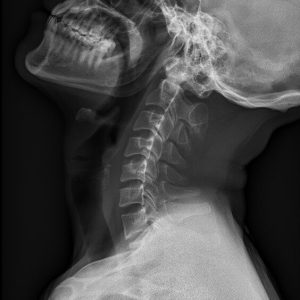

C spine Lat view